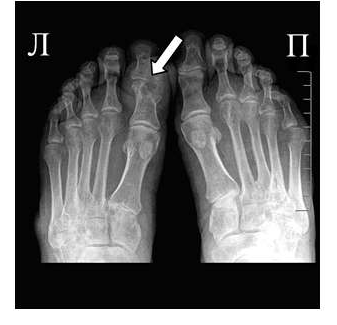

Эрозии при подагрическом артрите имеют округлую или овальную форму, часто со склеротическим ободком. Склеротический ободок вокруг внутрисуставного тофуса создает типичный для подагрического артрита симптом «пробойника» (см. рис. 1).

Рис. 2 Симптом «пробойника» в головках плюсневых костей обеих стоп в сочетании с вальгусной девиацией I плюсне-фаланговых суставов

Эрозии часто обнаруживаются в верхней и медиальной части плюсневой головки и часто в сочетании с вальгусной девиацией суставов. Типичным является асимметричность изменений (рис. 2).